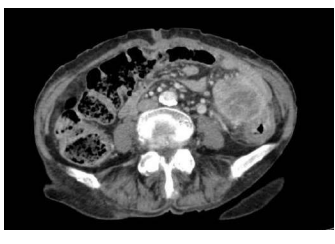

Uma paciente de 81 anos de idade, portadora de demência senil, hipertensão arterial, diabetes tipo 2 e artrite reumatoide, sem antecedentes familiares de neoplasia, deu entrada no pronto-socorro com dor abdominal em hipogastro e fossa ilíaca esquerda, sem irradiação há duas semanas, com piora progressiva. Estava em investigação por constipação intestinal com médico da unidade de saúde próxima à sua casa. Durante a investigação, realizou uma tomografia computadorizada de abdome total com contraste, que evidenciou a imagem abaixo.